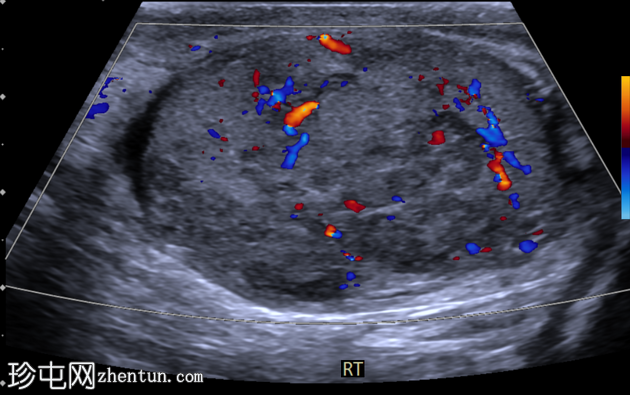

右侧睾丸内可见一大小约3.0 x 5.0 cm的异质性分叶状低回声肿块。肿块内未见囊性区域或钙化。彩色多普勒超声检查显示肿块内血流丰富。左侧睾丸正常。